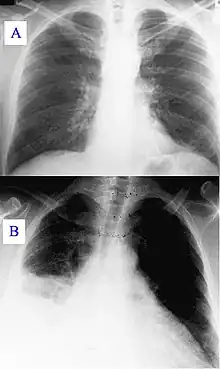

During its course, the disease can progress to an atypical pneumonia, which can result in a life-threatening acute respiratory distress syndrome, usually occurring during the first four to five days of infection.[7]